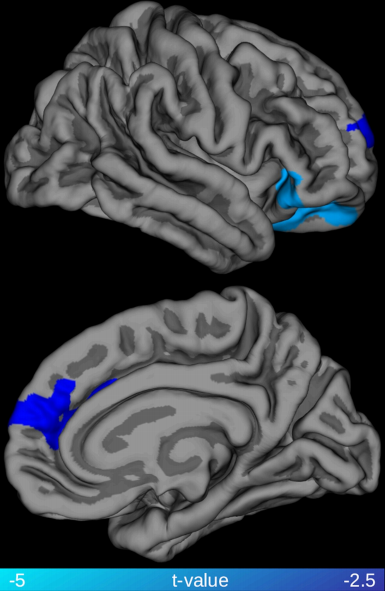

CSF和血浆中Nf-L的水平与额叶颞叶痴呆(FTD)等神经退行性疾病的变性有关,目前Nf-L被认为是FTD中最具潜力的诊断和预后生物标志物。尽管神经丝在健康神经系统中的位置和功能表明Nf-L升高与白质变性之间存在联系,但这种说法在体内尚未得到充分阐明。该研究通过将20名行为变异性FTD(bv FTD)患者的Nf-L血浆浓度与弥散张量成像(DTI)指标相关联,提供了Nf-L血浆水平与bvFTD患者白质变性之间具有关联性的证据。研究结果表明,血浆Nf-L浓度升高与广泛分布的白质束(包括上纵束,额枕束,前丘脑辐射和背扣带束)中的部分各向异性(FA)降低有关。血浆Nf-L浓度还与右侧内侧前额叶皮层和右侧外侧眶额叶皮层的一部分皮质变薄相关。上述结果支持以下假设:血液Nf-L水平反映了bvFTD中神经退行性疾病的整体水平,并有助于加深我们对FTD血液生物标志物与疾病过程之间相关性的理解。

图3. 全脑回归分析显示右内侧前额叶皮层和右外侧眶额叶皮层的皮质厚度与血浆Nf-L水平之间存在显著的负相关性。